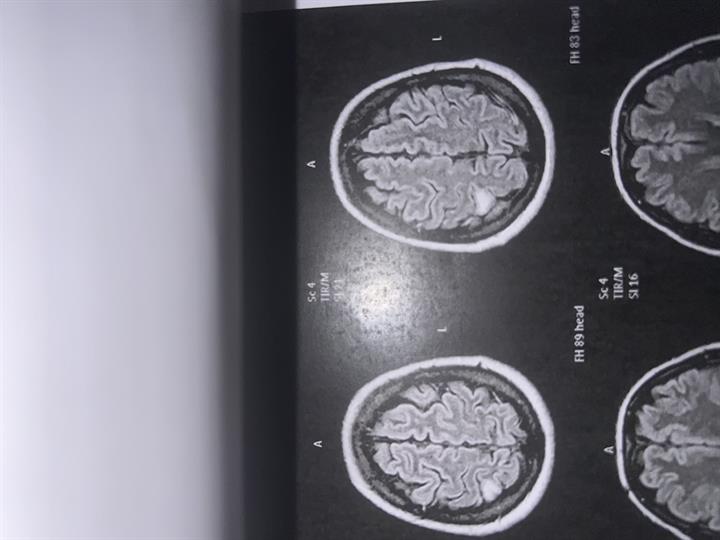

Ανάδειξη εστίας παθολογικής έντασης mr σήματος στο φλοιό του εγκεφάλου βρεγματικά δεξιά δίχως παθολογικό εμπλουτισμό μετά την ενδοφλέβια χορήγηση παραμαγμητικου σκιαγραφικού μέσου. (Δ/δ γλοιωτικη εστία)

Όλα βγήκαν καλά αλλά η γιατρος που μου έκανε το τριπλεξ κ είδε την μαγνητική μου είπε ότι μπορεί να είναι όγκος κ πρέπει σε 6 μήνες να ξανακάνω μαγνητική. Ο νευρολόγος ποτέ δε μου μίλησε για όγκου μου είπε μάλιστα ότι αν βγουν οι εξετάσεις καλές το αφήνουμε. Θα ήθελα την γνώμη σας.